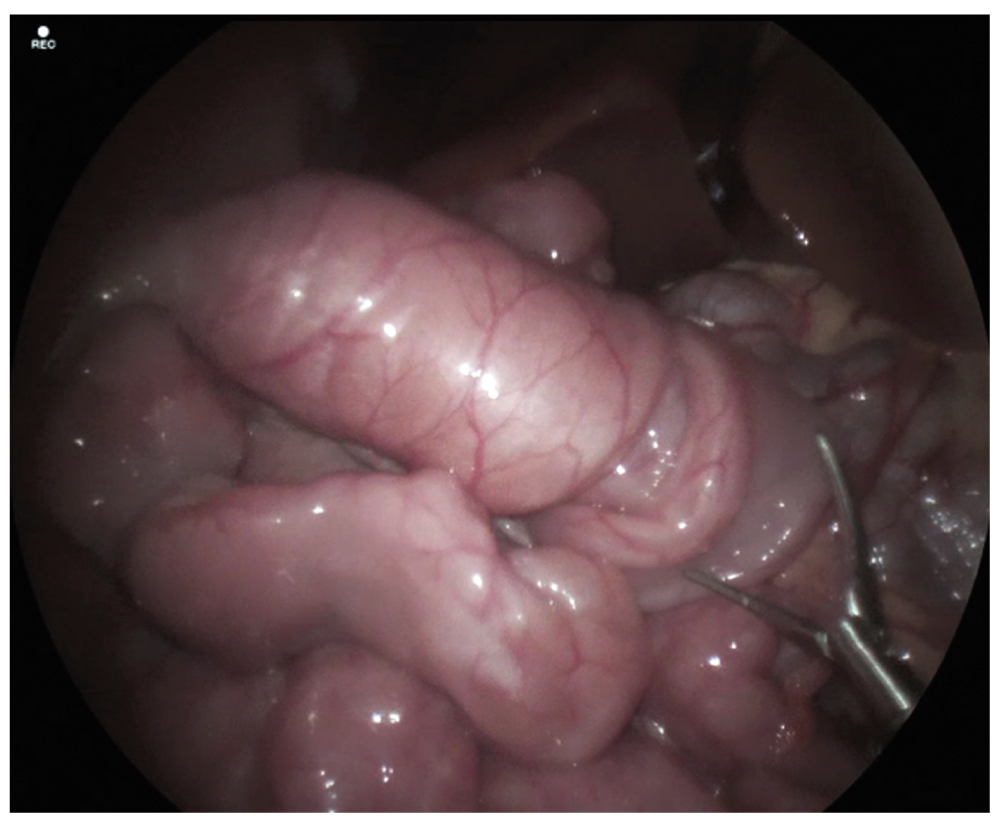

Консилиумом в составе детского хирурга, эндоскописта, педиатра было принято решение о необходимости диагностической лапароскопии для исключения внутрибрюшных и/или внутрипросветных причин ЖКК, которые, возможно, не были визуализированы при повторных эндоскопических исследованиях. Подготовка пациента включала коррекцию анемии путём гемотрансфузии эритроцитарной взвеси. После подготовки в условиях многокомпонентной эндотрахеальной анестезии выполнена диагностическая лапароскопия с ревизией тонкой кишки от илеоцекального угла до связки Трейтца, в ходе которой были обнаружены множественные транзиторные тонко-тонкокишечные инвагинаты, самостоятельно расправляющиеся во время исследования. На расстоянии около 30–40 см от связки Трейтца выявлена стойкая тонко-тонкокишечная инвагинация длиной до 10 см (рис. 5). Без технических трудностей при помощи тракции манипулятором инвагинат был расправлен, при осмотре внутреннего цилиндра заподозрено наличие внутрипросветного объёмного образования. Однако при инструментальной пальпации патологических объёмных образований в просвете кишки выявлено не было. При повторной детальной ревизии брюшной полости дивертикула Меккеля, патологических новообразований кишечника и других потенциальных источников кровотечения обнаружено не было.

Рис. 5. Лапароскопическая картина тонко-тонкокишечного инвагината

Fig. 5. Laparoscopic image of the small bowel intussusception